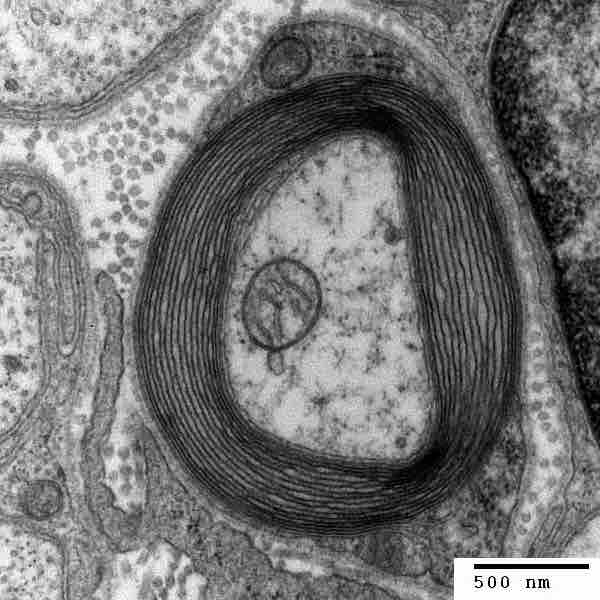

Transmission electron micrograph of a myelinated axon. The myelin layer (concentric) surrounds the axon of a neuron, showing Schwann cells.